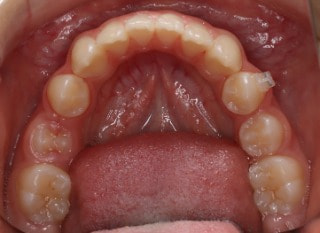

治療前

前歯装置装着時